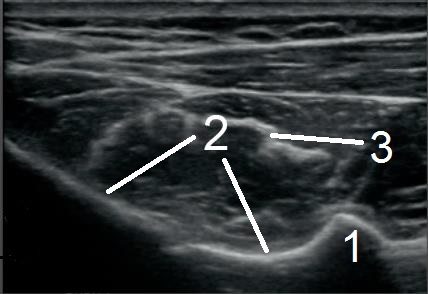

肩棘下筋横断位置1画像

位置1

筋腹の筋肉内中隔